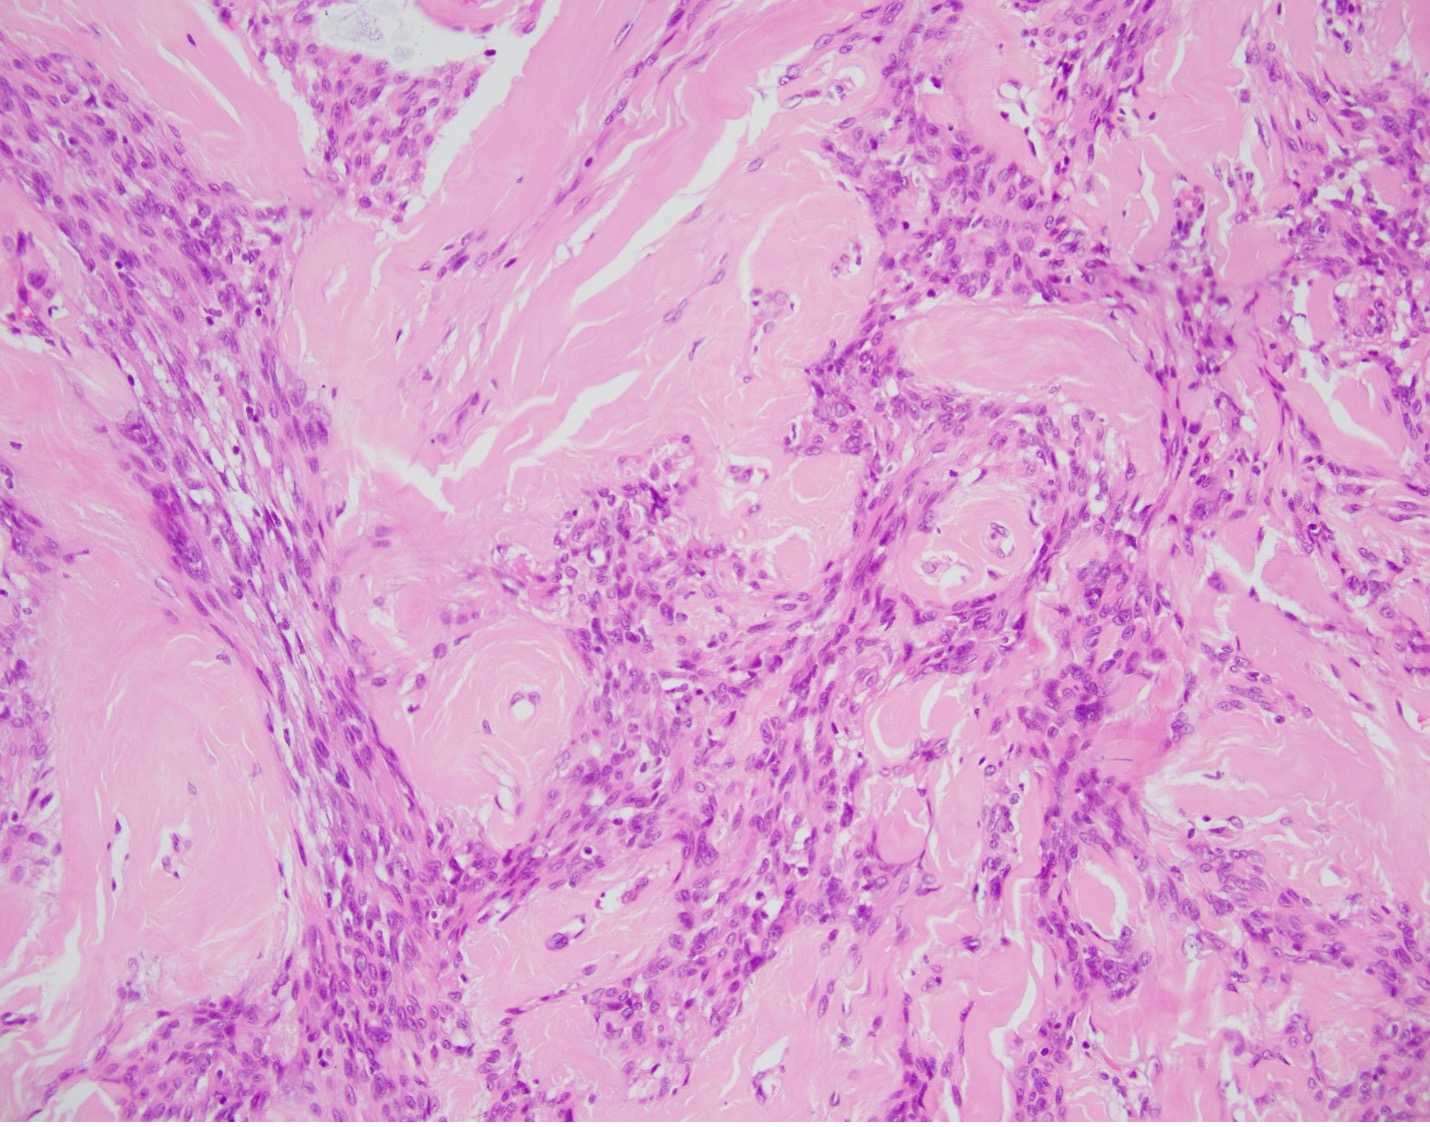

The patient is a 81-year-old male with a palpable breast mass. Imaging demonstrated an oval parallel mass with indistinct margins measuring 14 x 10 x 13 mm in the right breast at 1 o'clock located 1 cm from the nipple. A lumpectomy was performed and representative sections are shown.

Myofibroblastoma (MFB) is an uncommon myofibroblastic lesion, typically seen in older patients. It occurs in both males and females and usually presents as a slow growing, palpable, painless breast mass. Most lesions are small, 1-4 cm; however, cases of giant myofibroblastomas have been reported. Histologically, the lesion is characterized by a well-circumscribed mass composed of spindle cells intermixed between bundles of hyalanized collagen. Because the neoplasm is myofibroblastic in origin, immunohistochemical markers such as Smooth Muscle Actin (SMA), Muscle Specific Actin (MSA), and Desmin are characteristically positive. Myofibroblastomas are also typically positive for CD34, estrogen receptor (ER), progesterone receptor (PR), and androgen receptor (AR). The cells of interest are negative for cytokeratins. Genetically, the entity is characterized by loss of 13q14 and 16q. As a result, there is inactivation of genes RB1 and FOXO1, and as such, loss of Rb expression via immunohistochemistry. Treatment typically consists of surgical excision with no additional therapy required.

All of the other answer choices may be considered in the differential diagnosis, especially on biopsy. Metaplastic carcinomas can be comprised of spindle cells with or without an epithelioid component. However, the stromal collagen is typically not present and the cytology is much more pleomorphic with frequent mitosis and an infiltrative growth pattern. Additionally, metaplastic carcinomas will be positive for cytokeratin immunohistochemistry and negative for hormone receptors ER/PR/AR, CD34, and desmin/myofibroblastic markers. Phyllodes tumors are also neoplasms of stromal differentiation. Phyllodes tumors, however, show both the presence of spindle cells and benign epithelium, typically creating a “leaf-like” architecture. IHC is positive for CD34 but Rb staining is retained. Pseudoangiomatous stromal hyperplasia (PASH) usually doesn’t form a mass; however, it is a myofibroblastic lesion with a similar staining pattern, SMA, desmin, ER, and PR positive. Histologically PASH has a dense collagenous stroma with prominent slit-like spaces. Additionally, the characteristic genetic alterations found in MFB are not present.